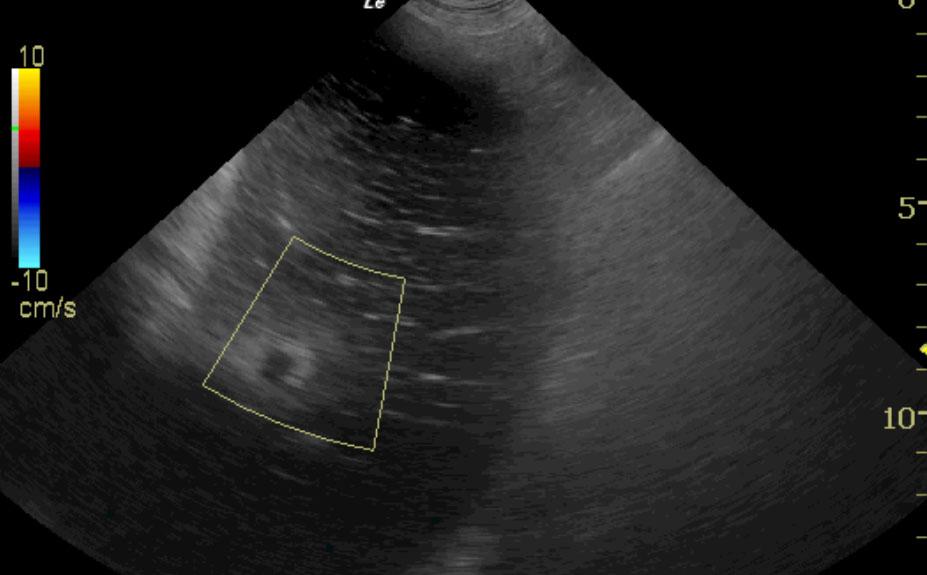

An intact 7-year-old female Great Dane dog presented for a history of vomiting and lethargy over a couple of days. At the previous assessment, anemia (32.5%), leukocytosis, and free fluid were present. On follow up assessment, the anemia had worsened (27.5%) and the leukocytosis was similar. ECG revealed VPCs. On cursory abdominal ultrasonography, free fluid and hyperechoic hepatic nodules were evident. The free fluid was found to represent a hemoabdomen.